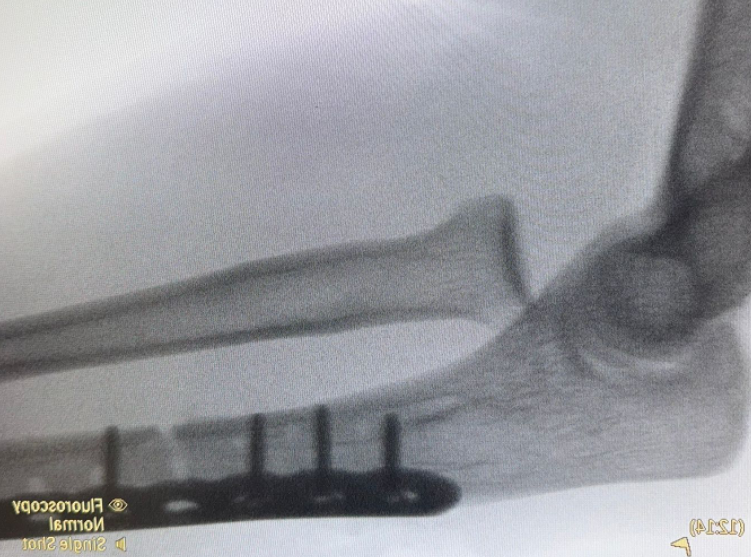

Ongoing anterior radial head dislocation after olecranon plating, treated with lateral approach and open reduction